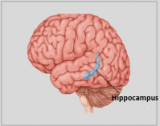

La neuroanatomie est la branche de l'anatomie qui étudie l'anatomie du système nerveux, c'est-à-dire la structure, la fonction et l'organisation du système nerveux.

Le système nerveux est l'un des systèmes les plus complexes du corps humain, et il comprend le cerveau, la moelle épinière, les nerfs périphériques et les ganglions nerveux. La neuroanatomie s'intéresse à la manière dont ces structures sont reliées les unes aux autres, comment les signaux sont transmis entre les cellules nerveuses, et comment les différentes parties du système nerveux travaillent ensemble pour contrôler les fonctions corporelles et cognitives. Les neuroanatomistes utilisent des techniques d'imagerie avancées, comme l'imagerie par résonance magnétique (IRM), la tomographie par émission de positons (TEP) et la microscopie pour visualiser les structures et les fonctions du système nerveux.